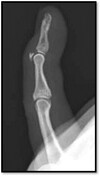

64

What pathology is shown here?

Mallet fracture